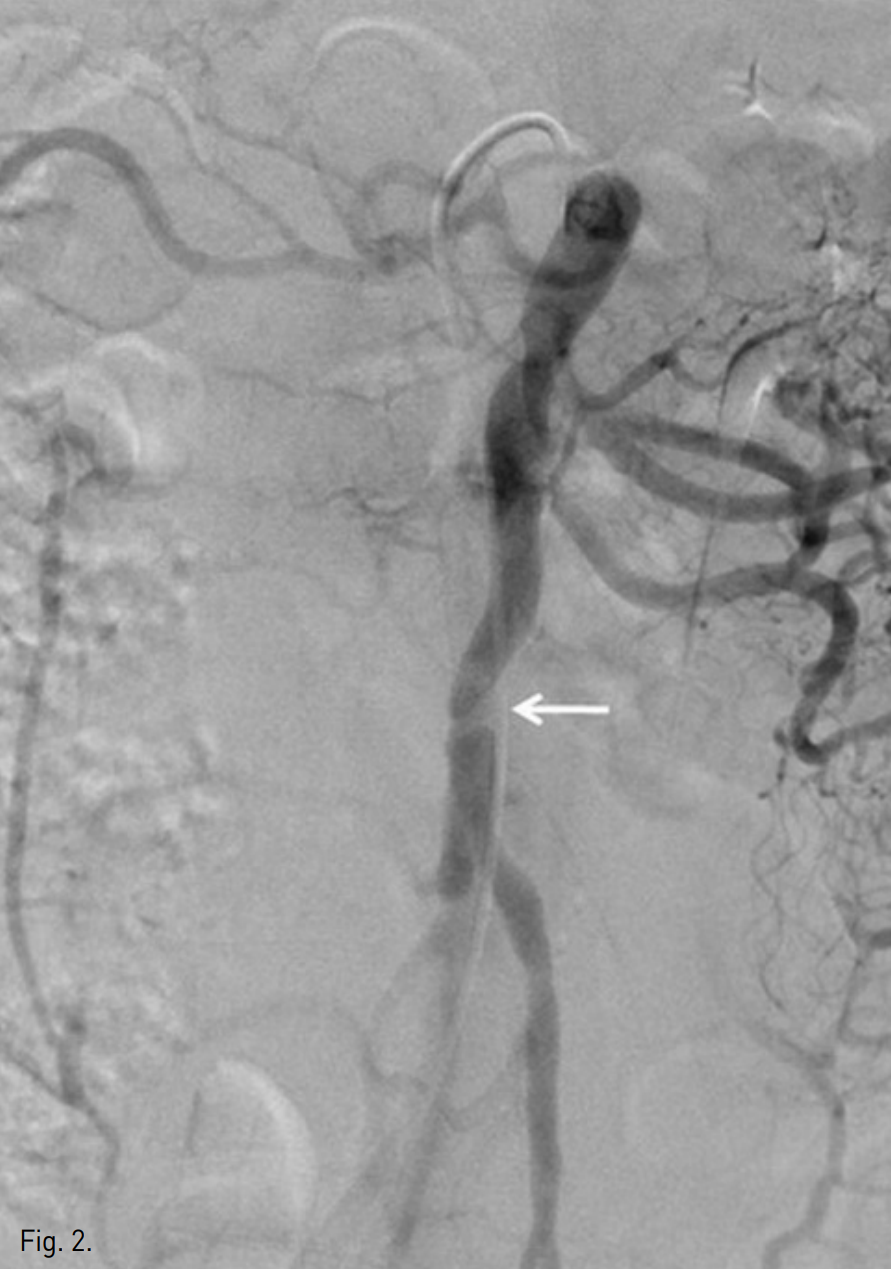

복부 CT에서 상장간막동맥(superior mesenteric artery, SMA)의 박리가 있었으며 중간결장동맥(middle colic artery)의 기시부가 경도로 좁아져 있고 가성 내강과 진성 내강의 혈류가 관찰되었다(Fig. 1). 같은 날 시행한 혈관조영술에서 상장간막동맥 기시부부터 회결장동맥(ileocolic artery) 분지부까지 침범한 동맥박리를 확인 하였다(Fig 2). 이 밖에 복강동맥과 하장간막동맥에는 특이 소견은 발견 되지 않았으나 변연 동맥 여러 곳이 동맥경화에 의한 좁아져 있었다. 소장과 대장의 동맥혈류가 유지되고 있어 스텐트삽입술은 시행하지 않았으며, 수축기 혈압 110mmHg, 심장박동 수 50~60회로 유지하며 보존적 약물치료를 하였다. 환자의 복통은 진정되었으며 7일 후 퇴원하였다. 5개월 후 추적검사로 시행한 복부 CT에서 상장간막동맥의 박리피판이 여전히 관찰되며 진성 내강과 가성 내강의 개통성을 확인할 수 있었고 기타 변연 동맥의 폐색은 없는 것이 확인되었다. 하지만 1년 추적 복부 CT에서는 가성 내강을 따라 혈전이 형성되었고(Fig. 3) 원위부로 혈관 폐색의 소견은 보이지 않았으며 장관의 허혈이나 경색 소견 또한 관찰되지 않았다. 2년 추적 CT에서 상장간막동맥은 정상화되었으며 박리나 동맥류 소견은 관찰되지 않았다.

Fig. 2

Arteriogram of SMA on the ini tial diagnosis shows the dissecting intimal flap involving from SMA orifice to ileocolic bifurcation (arrow).